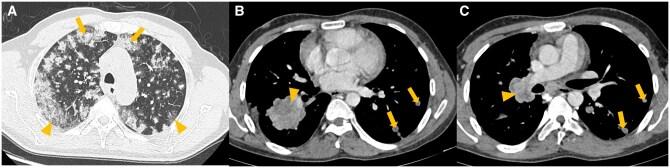

Lung cancer is the second most commonly diagnosed cancer worldwide. In the present era of targeted therapy for various lung cancer mutations, it is essential to be aware of the imaging correlates of various lung cancer mutations on contrast enhanced computed tomography of thorax. In this article, we have discussed the imaging patterns of various types of lung cancer including different mutations and also comprehensively reviewed the imaging recommendations (National Comprehensive Cancer Network [NCCN], European Society of Medical Oncology [ESMO] and American Society of Clinical Oncology [ASCO]) and management guidelines of lung cancer (non-small cell, small cell and other neuroendocrine tumours). We have also discussed guidelines for screening, diagnosis, staging (recent 9th edition tumour node metastasis [TNM]), treatment response evaluation, and follow up. Role of interventional radiology in the treatment of primary lung cancer, lung metastasis, and management of posttreatment complications, have also been described in detail in this article. In addition, current status of artificial intelligence in lung cancer has also been briefly discussed.

肺癌是全球第二大常见的确诊癌症。在当前针对各种肺癌突变进行靶向治疗的时代,了解胸部对比增强计算机断层扫描上各种肺癌突变的影像学关联至关重要。在本文中,我们讨论了包括不同突变在内的各种类型肺癌的影像学模式,并全面回顾了肺癌(非小细胞、小细胞和其他神经内分泌肿瘤)的影像学建议(美国国立综合癌症网络 [NCCN]、欧洲医学肿瘤学会 [ESMO] 和美国临床肿瘤学会 [ASCO])及管理指南。我们还讨论了筛查、诊断、分期(最新第9版肿瘤淋巴结转移 [TNM])、治疗反应评估和随访的指南。本文还详细描述了介入放射学在原发性肺癌治疗、肺转移以及治疗后并发症管理中的作用。此外,还简要讨论了人工智能在肺癌方面的现状。